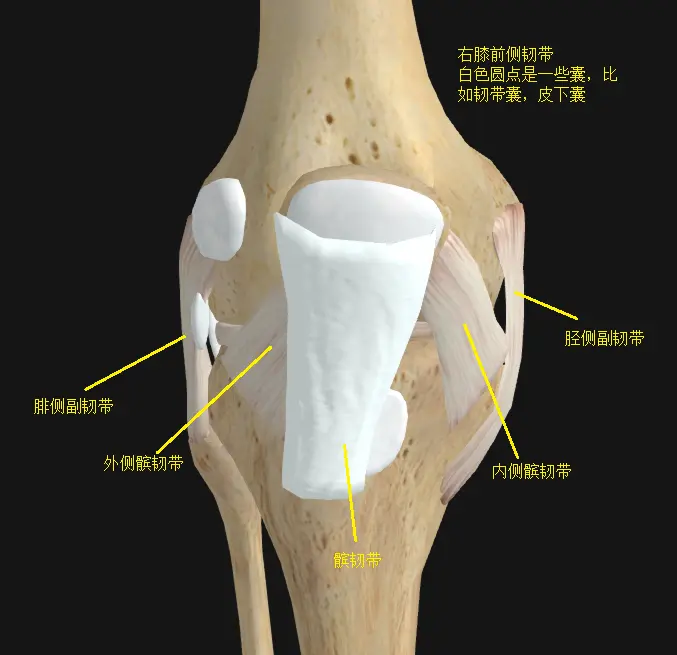

膝关节在功能解剖上有前侧伸膝功能的股四头肌和屈膝功能的缝匠肌,有后侧屈膝功能的半腱肌半膜肌,股二头肌,腘肌,腓肠肌。倒不是说没有在左右两侧跨越膝关节的肌肉(比如引起髂胫束综合征的阔筋膜张肌-髂胫束就是在外侧跨过了膝关节),而是膝关节周围有一圈不具备收缩性的韧带加固,使膝关节失去左右活动的能力,相应的获得了超强稳定性。

膝关节在功能解剖上有前侧伸膝功能的股四头肌和屈膝功能的缝匠肌,有后侧屈膝功能的半腱肌半膜肌,股二头肌,腘肌,腓肠肌。倒不是说没有在左右两侧跨越膝关节的肌肉(比如引起髂胫束综合征的阔筋膜张肌-髂胫束就是在外侧跨过了膝关节),而是膝关节周围有一圈不具备收缩性的韧带加固,使膝关节失去左右活动的能力,相应的获得了超强稳定性。

上述所有肌肉韧带的特点都是不具备膝关节左右活动,即外展内收功能的,膝关节周围的肌肉只有屈伸功能,以及“在屈膝位上,很少量的旋转功能”。它所有的构造(骨,软骨,韧带,肌肉,软组织等…)从上到下从内到外都是为了屈伸功能和承重服务的,这些解剖结构决定了在实际使用场景中,膝关节运动要避免旋转和左右两侧活动的力。

了解了膝关节的结构之后我们可以知道,膝关节的稳定性是由关节周围的肌肉韧带来完成的,在前后的屈伸过程中伸膝肌和屈膝肌可以控制动态稳定,而膝关节不存在外展内收功能,所以无法对膝关节左右方向上的稳定进行动态控制。如果出现了类似左右方向上的力,维持膝关节左右方向的静态稳定的任务会落到周围韧带上,于是韧带压力过大,这是我们不希望出现的事。